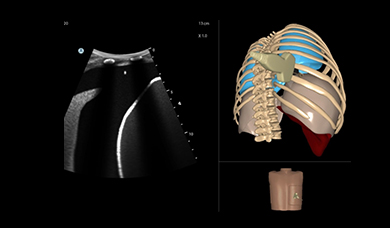

Simbionix Ultrasound Mentor is the answer to the growing need for ultrasound training among multiple medical specialties. This modular simulation platform enables easy manikin rotation (male, female, pediatric and interventional), and offers diverse applications for a range of specialties such as OB/GYN, Point-of-care Ultrasound (POCUS) and Echocardiography.

Ultrasound Mentor accelerates the development of basic to advanced technical and cognitive skills, by providing not only the probe manipulation training, but also a didactic environment enabling structured, self-guided learning including step-by-step instructions and educational aids such as 3D anatomical map and probe positioning assistant, all backed up with our progress monitoring tool MentorLearn.

EFAST and RUSH MODULE

Abdominal Module

Lung Module

Thoracentesis Module